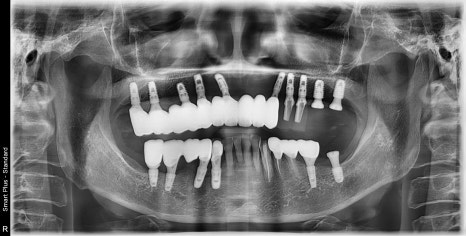

임플란트의 위치, 갯수, 방향을 위해 시뮬레이션을 해보았습니다.

뼈의 끝부분이 뾰쪽해지면서 임플란트를 식립하기 위해서는

상부의 골을 다듬고 임플란트 식립후

치조골이식술을 통해 임플란트 주변 골의 두께를 충분히 확보해 주는것이 좋습니다.

수술을 하시고, 기존 쓰시던 틀니를 임시로 쓰시면서

뼈와 임플란트가 고정이 생길때까지 기다리는 시간을 갖습니다.